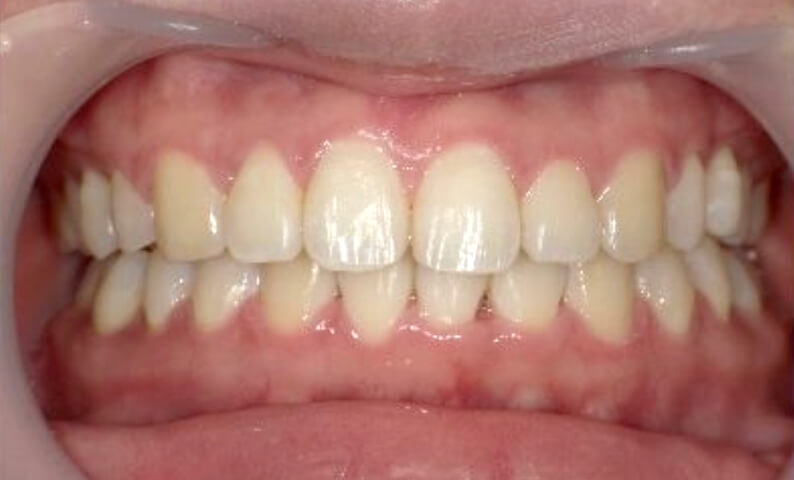

症例_024 上下顎の部分矯正

治療期間:13ヶ月金額:51万円+税女性前歯のガタガタ八重歯

| Before | After |

|---|---|